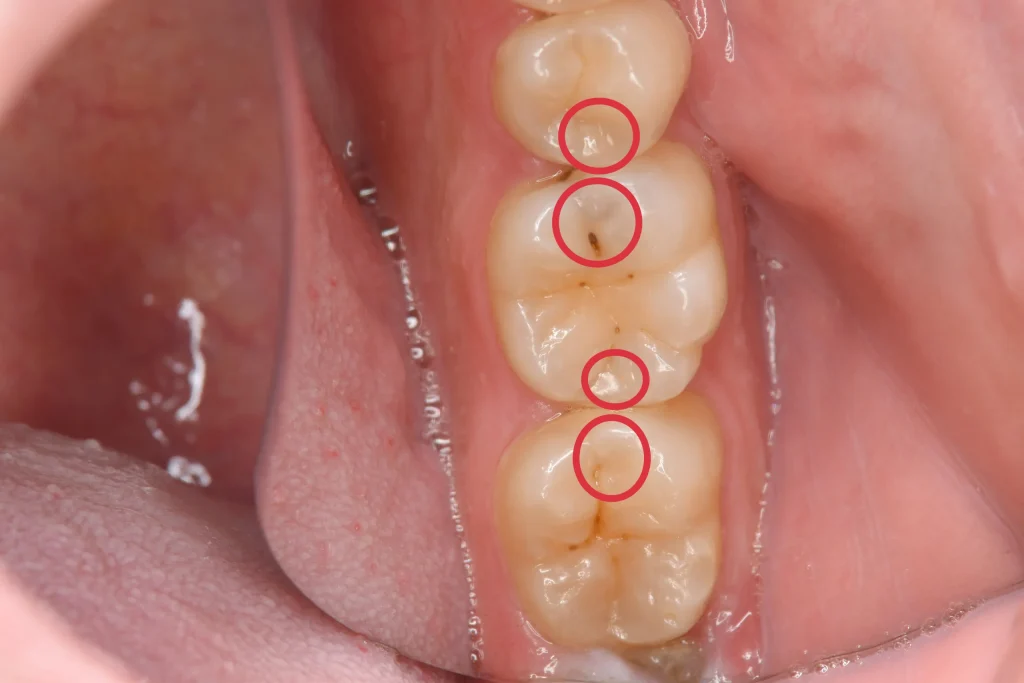

気になるところがあるとのことで来院された患者様です。

レントゲン検査にて隠れた虫歯が見つかったため、患者様と相談しダイレクトボンディングで治療することとなりました。

赤丸部が隠れた虫歯です。